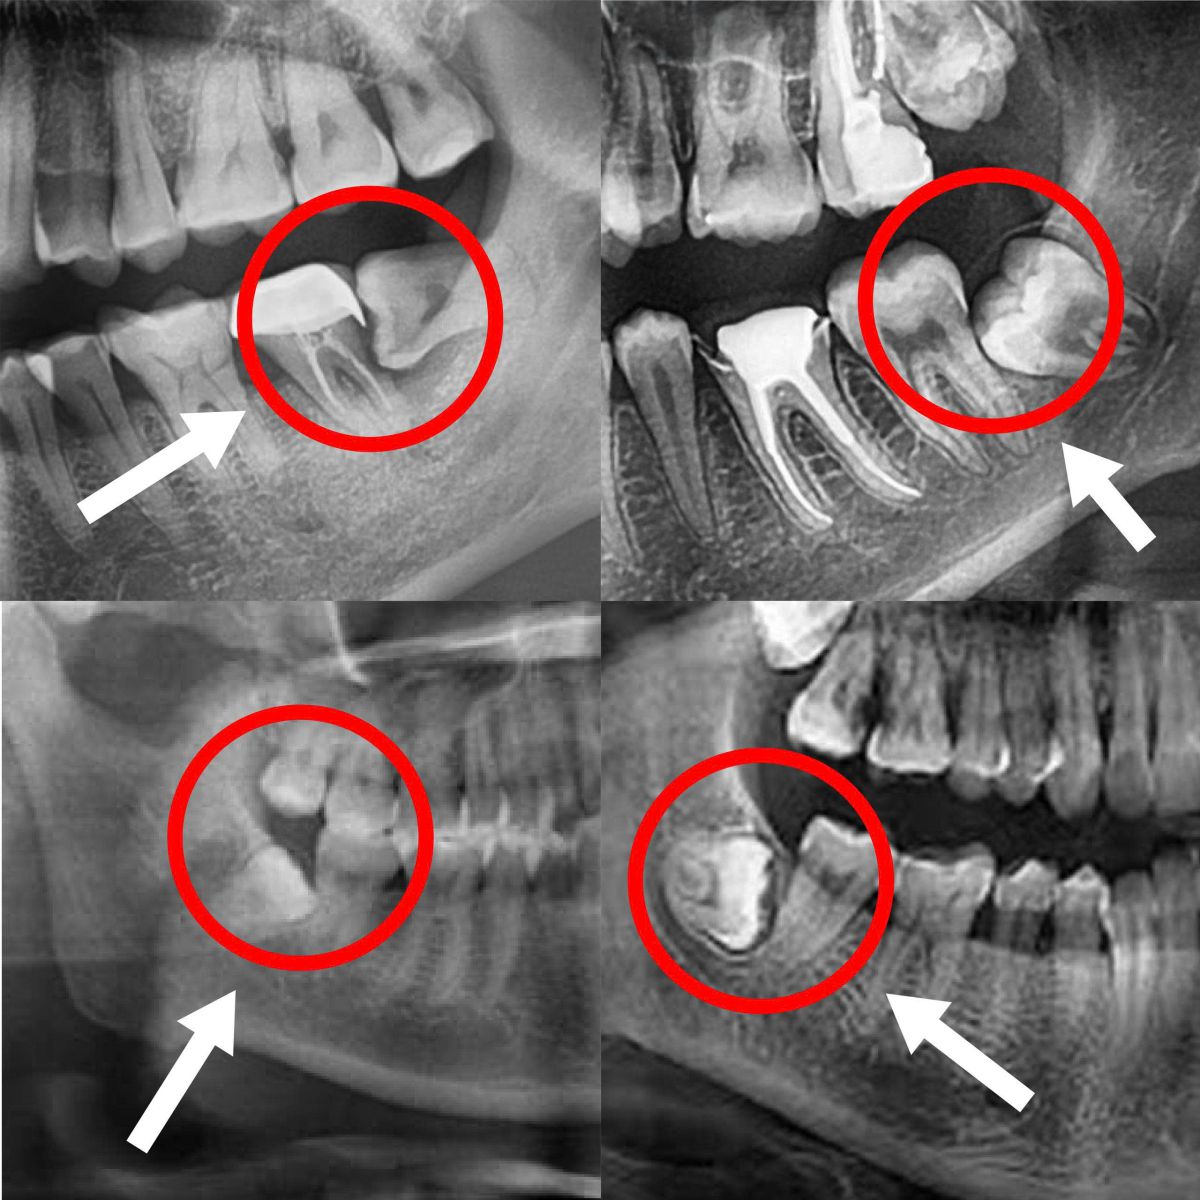

Răng khôn là những chiếc răng mọc sau cùng trên cung hàm, thường xuất hiện khi xương hàm đã phát triển ổn định. Chính vì vậy, răng khôn thường không đủ chỗ để mọc thẳng, dễ mọc lệch, mọc ngầm và gây ra hàng loạt vấn đề răng miệng.